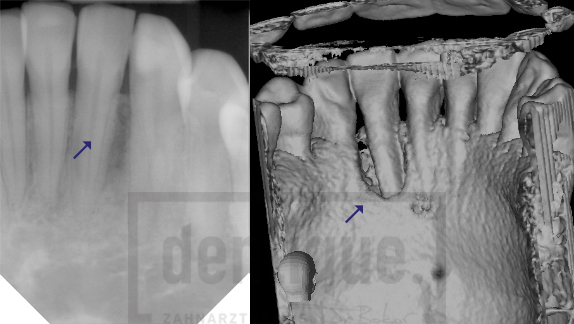

Im Gegensatz zu herkömmlichen zweidimensionalen Röntgenaufnahmen liefert die DVT detailreiche und präzise 3D-Bilder. Dadurch können Diagnosen genauer gestellt und Behandlungen deutlich sicherer geplant werden.

Ein herkömmliches 2D-Röntgenbild ist seit Jahrzehnten ein bewährtes diagnostisches Instrument. Dennoch kann es in bestimmten Fällen zu unklaren oder schwer interpretierbaren Befunden kommen.

Da bei einer zweidimensionalen Aufnahme komplexe Strukturen übereinander projiziert werden, können wichtige Details verdeckt bleiben. Dies betrifft insbesondere:

Die DVT vermeidet diese Überlagerungen. Knochen- und Zahnstrukturen lassen sich aus verschiedenen Blickwinkeln betrachten, wodurch selbst kleinste Veränderungen zuverlässig erkannt werden können.